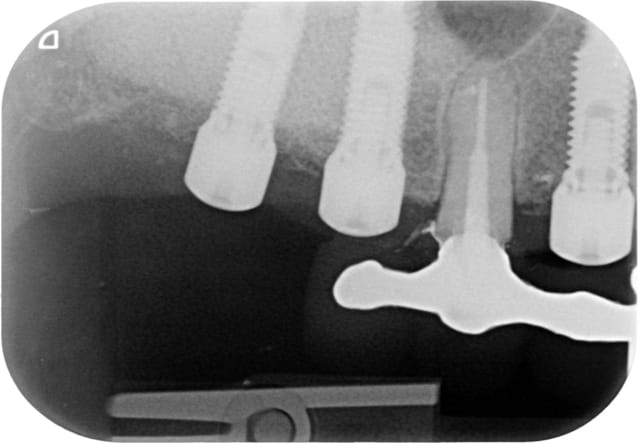

Voici la radio lors de la pose.

je ne pense pas, l'occlusion a été réglé le jours de la pose.